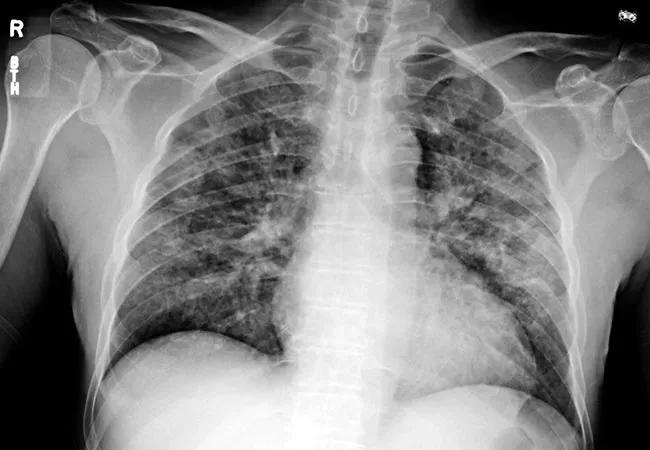

Chest images from a patient who ended up in the ICU with suspected lung injury related to vaping.

Chest images from a patient who ended up in the ICU with suspected lung injury related to vaping. The images show improvement of lung opacities with no specific treatment other than avoiding exposure while in the hospital.